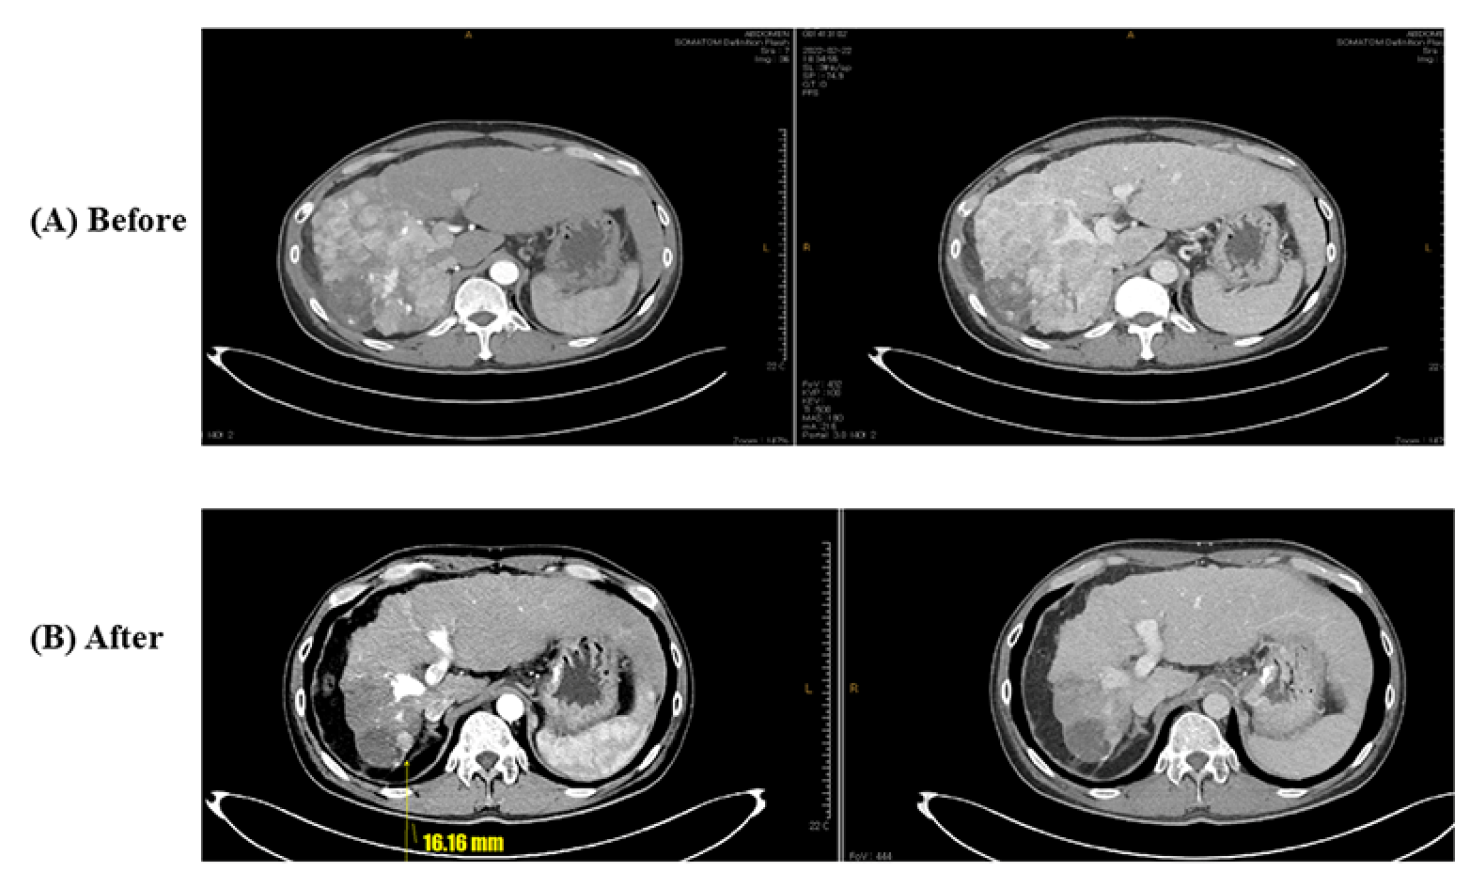

- Case 1